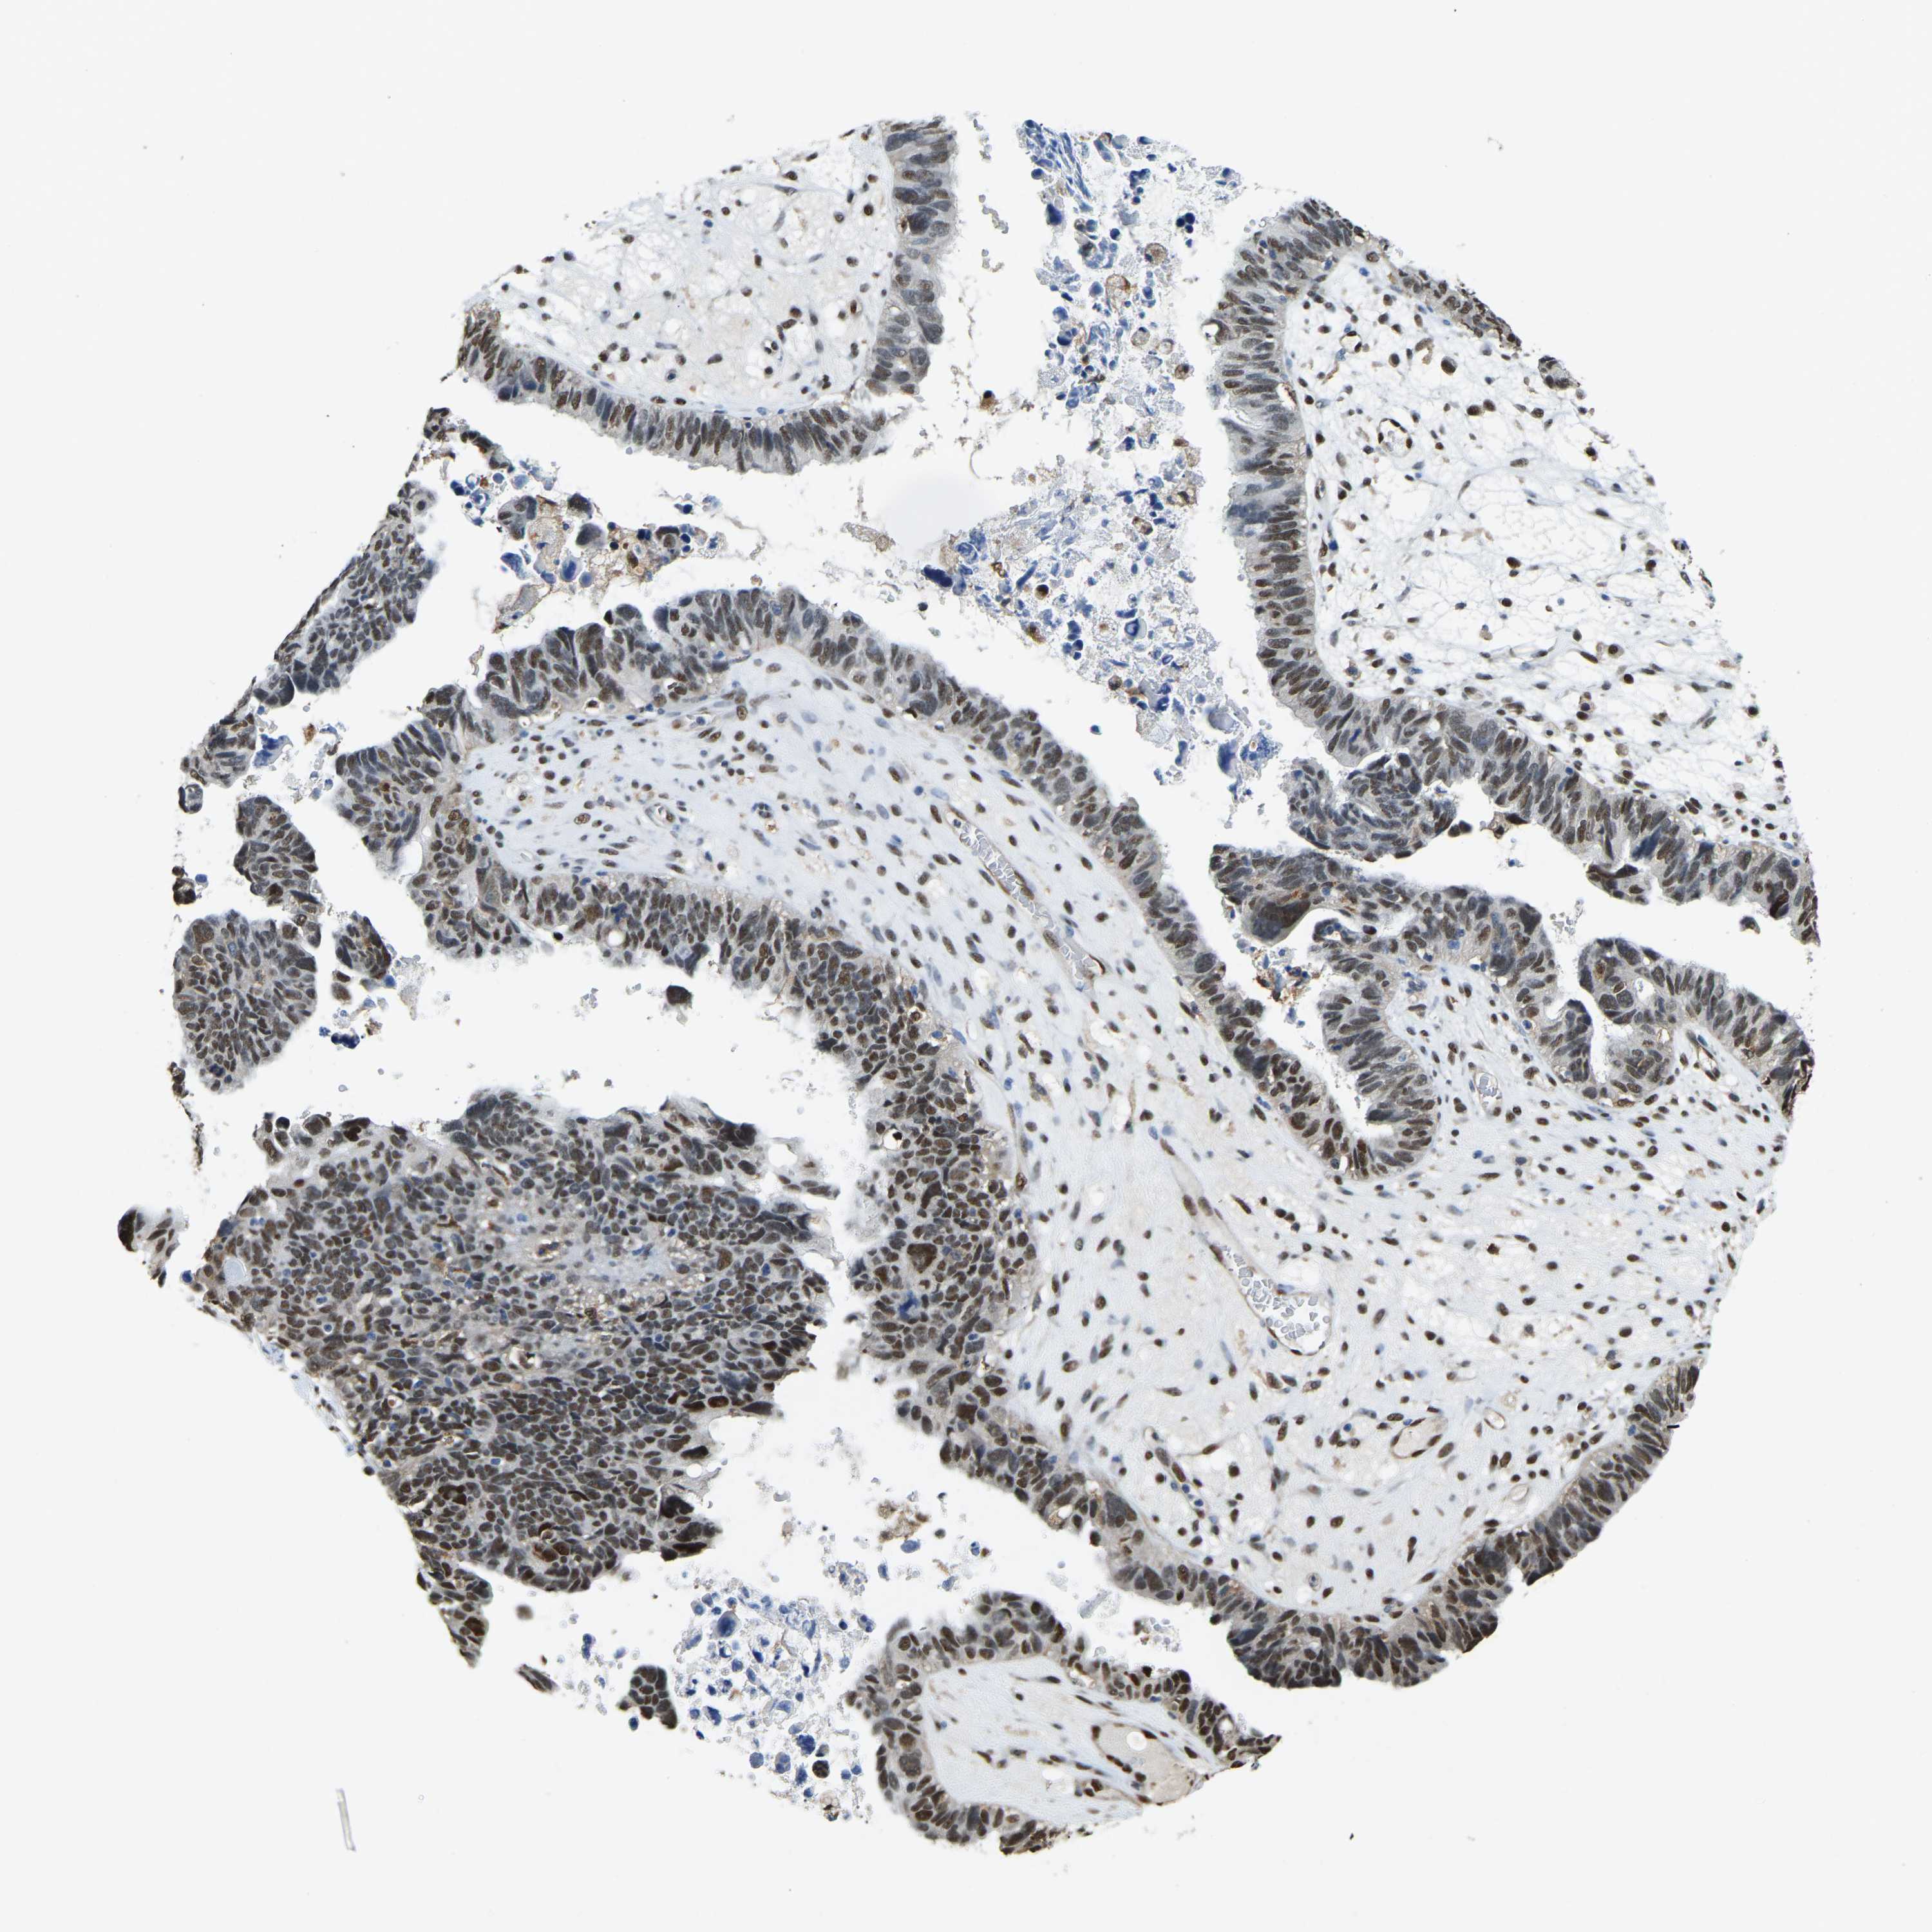

OVARIAN CANCER - Protein expressioni

A mouse-over function shows sample information and annotation data. Click on an image to view it in a full screen mode. Samples can be filtered based on level of antibody staining by selecting one or several of the following categories: high, medium, low and not detected. The assay and annotation is described here.

Note that samples used for immunohistochemistry by the Human Protein Atlas do not correspond to samples in the TCGA dataset.

Antibody stainingi

Antibody staining in the annotated cell types in the current human tissue is reported as not detected, low, medium, or high, based on conventional immunohistochemistry profiling in selected tissues. This score is based on the combination of the staining intensity and fraction of stained cells.

Each image is clickable and will lead to virtual microscopy that enables deeper exploration of all samples and also displays staining intensity scores, fraction scores and subcellular localization as well as patient and tissue information for each sample.

Antibody HPA019223

Staining

High

Medium

Low

Not detected

Intensity

Strong

Moderate

Weak

Negative

Quantity

>75%

75%-25%

<25%

None

Location

Nuclear

Cytoplasmic/membranous

Cytoplasmic/membranous,nuclear

Cystadenocarcinoma, serous, NOS

Carcinoma, endometroid

Cystadenocarcinoma, mucinous, NOS

Carcinoma, NOS